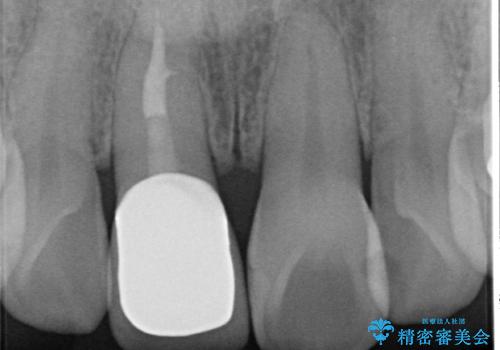

以前に神経が死に、根管治療を行った歯の変色が認められたためセラミックによる審美補綴治療を計画します。

- 16万円(仮歯・ファイバーコア・ジルコニアクラウンスペシャル)費用は治療当時の料金となります

神経治療を行い補綴(かぶせもの)治療を行わないと、変色が目立ち審美障害を起こすことがあります。

このような場合、セラミックによる審美改善が治療の一案として提案されます。